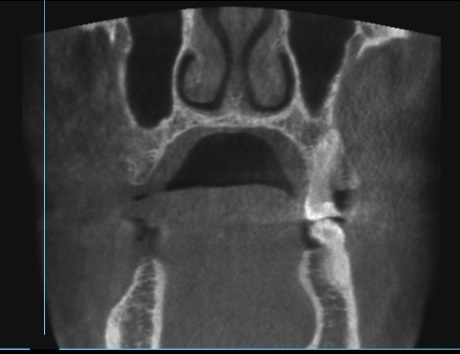

Пропила 2 курса антибиотиков. Хирург сказал, что все зубы в порядке, и отправил домой нервы лечить. Рентгенолог увидела повреждения и сказала не есть больной стороной и вообще не жевать. Это избавило меня от постоянной боли. Но стоит только дотронуться до семёрки, появляется неприятное очущение, как будто он висит на волоске. И в месте удалённой 5 зуд. Как будто кость сломана. Фото с 3д рентгена во время курса антибиотиков.

По этому снимку можно сказать, что немного повреждена передняя стенка, но это не является проблемой. К хирургу обратиться стоит, для того чтобы оценить процесс заживления.